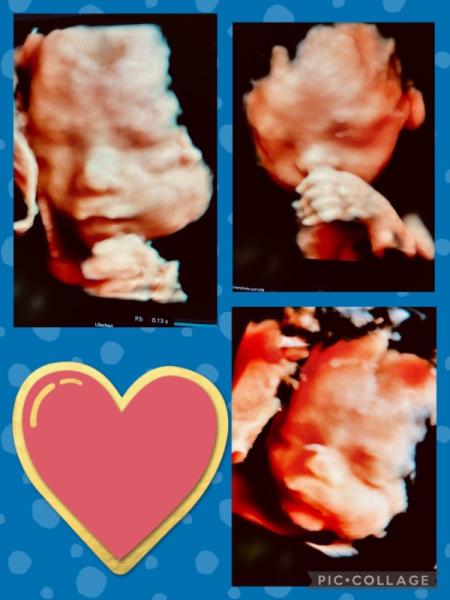

Heute war ich wieder, parallel zu meinen Terminen beim FA, in der Frauenklinik zum großen Ultraschall (wird bei mir dort ebenfalls im 4 Wochenrhythmus gemacht). Heute wurde unser kleiner Mann auf ca. 800g geschätzt und ca. 31cm. Alles soweit unauffällig. Ich habe ein paar schöne Fotos bekommen.

Hier nochmal ein paar Fotos

Guten Morgen, das sind wundervolle Bilder von eurem Schatz. So ein hübsches Gesicht. Das war der dritte Ultraschall, oder? Meinen habe ich nächste Woche und bin schon ganz gespannt.